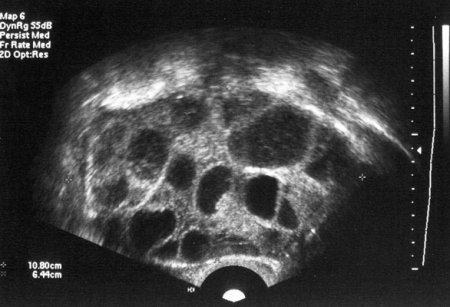

Узі в першому триместрі вагітності норми

УЗД в першому триместрі При постановці на облік жінці призначають обстеження, до якого, крім аналізів і консультацій фахівців входить і ультразвукове дослідження ембріона, матки і придатків. Перше УЗД,

21 тиждень вагітності - УЗД На 18-21 тижні жінці призначають обов'язкове друге скринінгове обстеження. Так як тільки